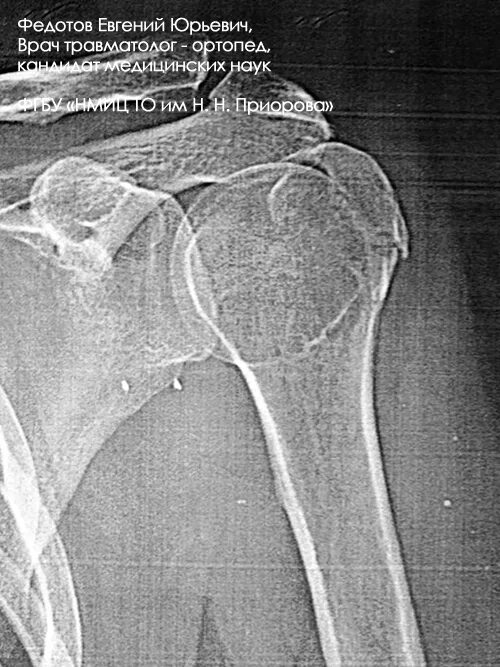

Перелом б бугорка